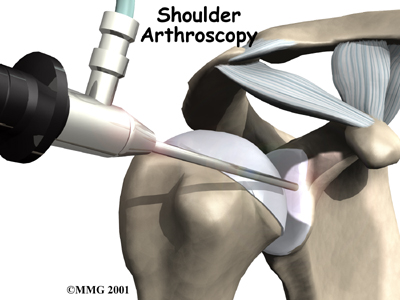

A surgeon may need to examine your shoulder using an while you are under general anesthesia, which puts you to sleep. An arthroscope is a tiny TV camera inserted into the shoulder through a small incision.

A surgeon may need to examine your shoulder using an while you are under general anesthesia, which puts you to sleep. An arthroscope is a tiny TV camera inserted into the shoulder through a small incision.

This allows a good look at the muscles and ligaments of the shoulder. When you are awake, it is hard to test the ligaments because you automatically tighten the muscles during the exam.

Surgery on the shoulder has improved dramatically over the past two decades. many of the procedures that have been developed in the past have been abandoned altogether. Today, surgery that is performed for stabilizing an unstable shoulder is most commonly done using the arthroscope.

The arthroscope has changed all that.

An arthroscope is a special type instrument designed to look into a joint, or other space, inside the body. The arthroscope itself is a slender metal tube smaller than a pencil. Inside the metal tube are special strands of glass called fiberoptics. These small strands of glass form a lens that allows one to look into the tube on one end and see what is on the other side - inside the space. This is similar to a microscope or telescope. In the early days of arthroscopy, the surgeon actually looked into one end of the tube. Today, the arthroscope is attached to a small TV camera. The surgeon can watch the TV screen while the arthroscope is moved around in the joint. Using the ability to see inside the joint, the surgeon can then place other instruments into the joint and perform surgery while watching what is happening on the TV screen.

The arthroscope lets the surgeon work in the joint through a very small incision. This may result in less damage to the normal tissues surrounding the joint, leading to faster healing and recovery. If your surgery is done with the arthroscope, you may be able to go home the same day.

To perform the Bankart type repair using the arthroscope, several small incisions are made to insert the arthroscope and special instruments needed to complete the procedure. These incisions are small, usually about one-quarter inch long. It may be necessary to make three or four incisions around the shoulder to allow the arthroscope to be moved to different locations to see different areas of the shoulder.

A small plastic, or metal, tube is inserted into the shoulder and connected with sterile plastic tubing to a special pump. Another small tube allows the fluid to be removed from the joint. This pump continuously fills the shoulder joint with sterile saline (salt water) fluid. This constant flow of fluid through the joint inflates the joint and washes any blood and debris from the joint as the surgery is performed.